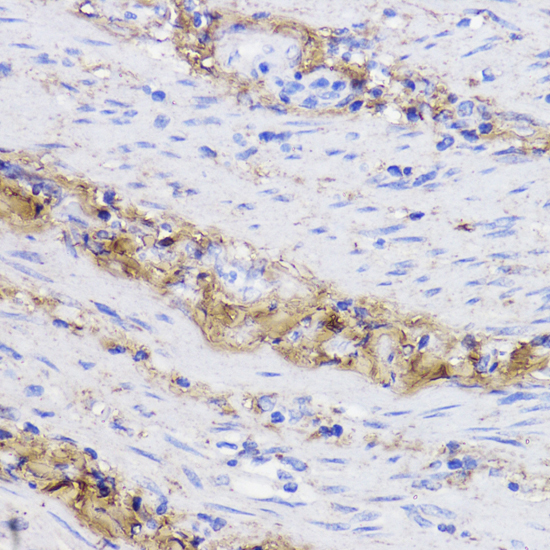

Immunohistochemistry of paraffin-embedded human colon carcinoma using COL1A1 antibody.

Immunohistochemistry of paraffin-embedded human placenta using COL1A1 antibody.

Immunohistochemistry of paraffin-embedded rat ovary using COL1A1 antibody.